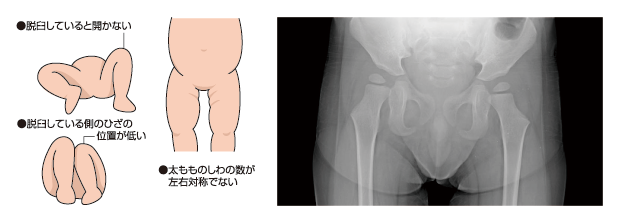

赤ちゃんの股関節脱臼 ―正しい知識と早期発見のために―日本小児整形外科学会。

乳幼児の股関節が脱臼しているサイン 先天性股関節脱臼幹整体院・みき接骨院 名古屋鳴子本院。

発育性股関節形成不全」の話。

↑保存マークで、脱臼の資料をいつでも見返せます🌸ぜひ🥹 ということで、 ミーコちゃんは ☆足のシワが非対称 ☆冬生まれの女の子 ということで、大きい病院に紹介になりました🥹 結果、脱臼してなかったー!✨ よかったー🥹✨ ただし脱臼しやすい形をしているそうで。

赤ちゃんの太ももの左右シワの違いから乳児股関節脱臼の疑いありと健診で診断され東大病院で精密検査 レントゲン診察の結果はいかに。えどりずむ。